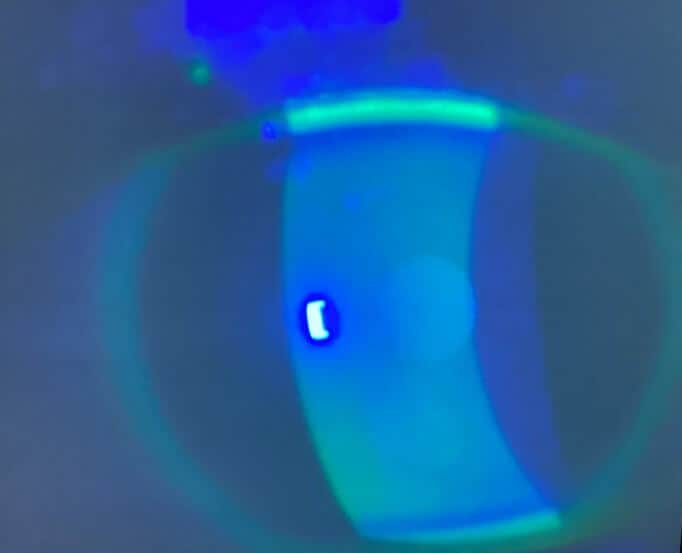

A 44-year-old female established patient was referred to the specialty anterior segment clinic for an evaluation due to unusual symptoms. She described a feeling of “a cold suction cup” on her right eye. The pertinent ocular history of the patient included decreased vision in her left eye due to optic atrophy from a childhood cystic lesion compressing the left optic nerve. There was no other pertinent medical or ocular history. Her surgical history included dental surgery, specifically a right upper impacted wisdom tooth extraction performed five years prior. The patient reported that a nerve was affected during the procedure and that she experienced severe pain on the right side of her face soon after the procedure. The intense pain continued for five years and was unsuccessfully treated with oral medications. The patient underwent a right-sided open skull base craniotomy for microvascular decompression of the trigeminal nerve to treat the trigeminal neuralgia. The patient reported experiencing right-sided facial numbness, intermittent blurry vision, and an uncomfortable right eye, with the inability to tear in the right eye soon after the procedure. Upon ocular examination, best-corrected visual acuity was 20/40 in the right eye, while the left eye showed no light perception. The left eye vision was stable, but her right eye vision had been 20/20 in prior eye exams. The right pupil was round and reactive to light, and a 4+ afferent pupillary defect was detected in the left eye, which was attributed to the left optic atrophy which was present since childhood. Confrontation visual field testing found a full-to-finger-count vision in the right eye, and the patient could not perform the test with her left eye. The sensitivity of the trigeminal nerve was assessed using a wispy cotton tip applied to the patient’s face and cornea. The patient was able to feel the cotton wisp on the left side of her face and cornea. However, she reported no sensation when the wisp was moved to the right side of her face (forehead, cheek) and cornea. She had some sensation on the lower right jaw. Slit lamp findings showed an intrapalpebral oval band of significant epithelial keratitis in the right eye, which stained with fluorescein but not with Rose Bengal. The stroma was intact and unremarkable. There was no keratitis noted in the left eye. A Schirmer’s test yielded results of 5 mm for the right eye and greater than 15 mm for the left eye. An InflammaDry test, which evaluates MMP9 levels in the tear film, was performed, yielding positive results in both eyes. Additionally, the proparacaine challenge test was performed, which did not improve her symptoms of a “suction cup” sensation. Intraocular pressures were within normal limits. A dilated fundus examination was unremarkable in the right eye and revealed a longstanding pale left optic nerve. A stage 2 neurotrophic keratitis was diagnosed in her right eye with a component of neuropathic pain. Multiple treatment options were discussed, including the placement of an amniotic membrane in the right eye. However, the patient was hesitant to proceed with this option since it was her only seeing eye. Cenegermin-bkbj 0.002% was prescribed to be used six times a day for eight weeks to address the neurotrophic keratitis in the right eye. Regular use of preservative-free artificial tears, spaced out at least 15 minutes with the cenegermin, was advised.

Figure 2. Corneal findings 6 months after treatment for eight weeks with cenegermin-bkbj and subsequent autologous serum.